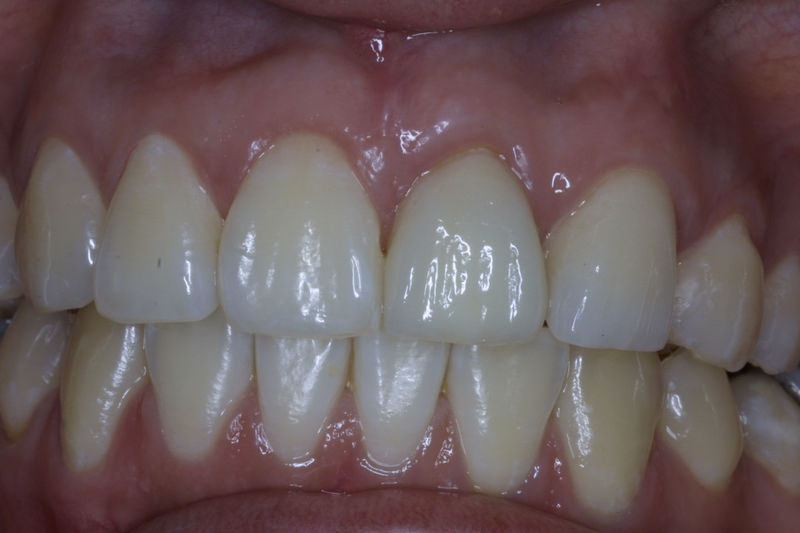

Amplia gama de tratamientos para mejorar la apariencia de la sonrisa, corrigiendo el color, la forma, el tamaño, la alineación y la posición de los dientes. Los procedimientos más comunes y solicitados incluyen el blanqueamiento dental, las carillas y coronas, así como las resinas.

Restauraciones fabricadas en el laboratorio con materiales estéticos, los cuales cubren de manera total dientes anteriores y posteriores. Se utilizan primariamente para restaurar dientes con caries, fracturas y/o defectos amplios, así como soportes de puentes. Para poder enviar el caso al laboratorio se toman impresiones utilizando materiales de impresión o técnicas modernas digitales.

Implante fracasado, extracción, carillas, coronas y prótesis fija.

Implantes, ortodoncia y coronas.

Ortodoncia y coronas.

Cirugía ortognática, implantes, carillas y coronas,